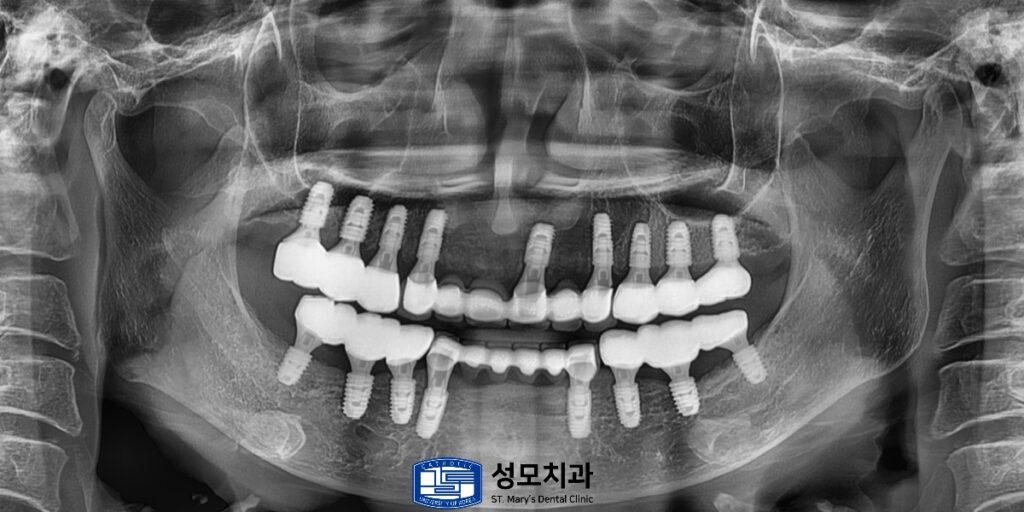

중간 기둥을 세우고 임시치아가 들어간 모습입니다.

기존에 뼈를 확보한 부분이

이제는 완전히 융합되어 임플란트 주변

안정적이게 감싸고 있는 것을 볼 수 있습니다.

보철까지 모두 완료된 모습입니다.

하치조 신경관까지의 충분한 거리를 확보하여

임플란트를 식립하였기 때문에

신경 손상 등의 부작용이 전혀 발생되지 않았습니다.